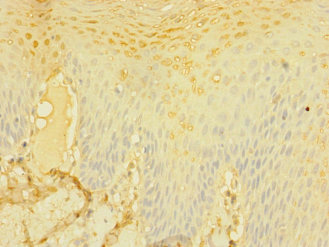

Immunohistochemistry of paraffin-embedded human tonsil tissue using CSB-PA618996ESR2HU at dilution of 1:100